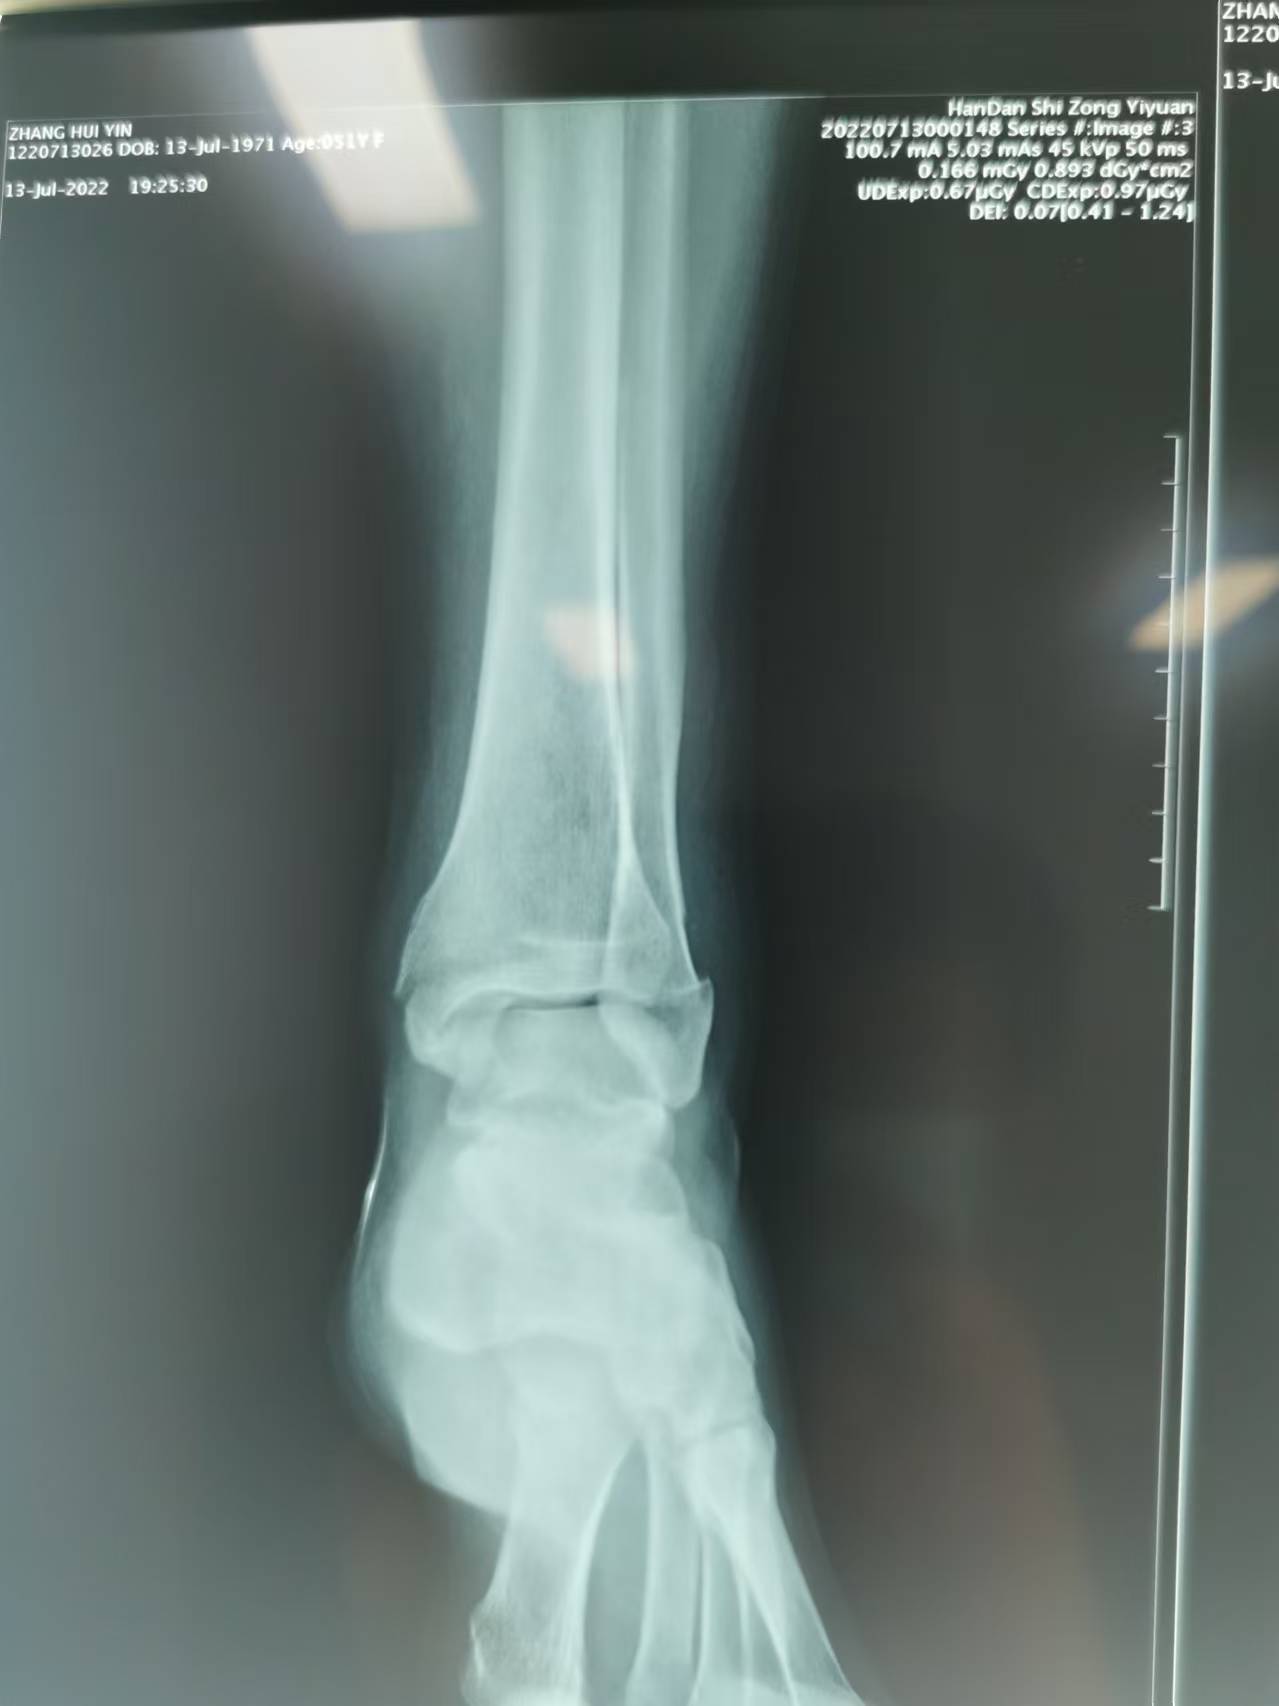

首页 > 张恒云工作室 > 影像资料 四